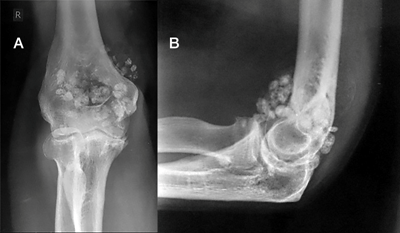

A: Rx AP y B: RM coronal en T1. Calcificación sobre el origen de los tendones flexores, por tendinitis crónica.

condromatosis

La condromatosis sinovial es una patología benigna, infrecuente, de etiología desconocida en la que se desarrolla una metaplasia cartilaginosa del tejido sinovial. Se caracteriza por la formación de nódulos que son liberados en la cavidad HÚMERO rticular. El tratamiento consiste en la extracción de los cuerpos libres intraarticulares, preferentemente por vía artroscópica.